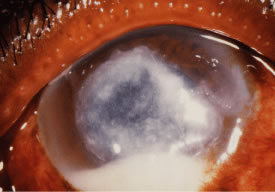

Candida infection typically produces epithelial ulceration, focal necrotizing stromal inflammation, moderate cellular infiltrate and edema in the adjacent stroma, and mild or moderate iritis in the early stages, indistinguishable from bacterial keratitis (Figs. 15, 16, and 17). Fungal elements cannot be detected by biomicroscopy. If untreated, the keratitis evolves to produce dense suppuration and necrosis of the deep stroma. Although multifocal suppuration may develop in polymicrobial keratitis, there is no distinctive sign of mixed Candida and bacterial infection (Fig. 18).

Advanced, severe filamentous fungal or yeast keratitis is indistinguishable from keratitis caused by virulent bacteria such as Staphylococcus aureus or Pseudomonas aeruginosa. The area of epithelial and stromal ulceration is large. Dense, opaque, homogenous, yellow-white stromal necrosis develop and is surrounded by confluent cellular infiltrate and full-thickness stromal edema (Figs. 19, 20, 21). Hyphal elements may penetrate Descemet's membrane and endothelium and be visualized in the anterior chamber. Fibrinous material accumulates over the endothelium, anterior chamber angle, and iris. Pain is typically severe. Secondary ocular hypertension may ensue. Progressive stromal necrosis leads to corneal perforation and, rarely, consecutive endophthalmitis.